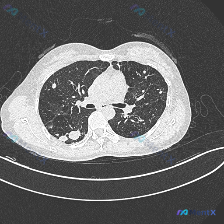

看到这个CT影像,整理了分析思路分享给大家。 病例影像核心信息 本次提供的是胸部CT肺窗横断面影像,核心异常总结: 1. 双肺透亮度显著降低,整体呈现弥漫性磨玻璃密度增高,也就是典型的「毛玻璃样」肺野改变 2. 磨玻璃背景下,双肺广泛分布散在细小的粟粒状/类粟粒状微小结节 3. 气管、主支气管结构大...